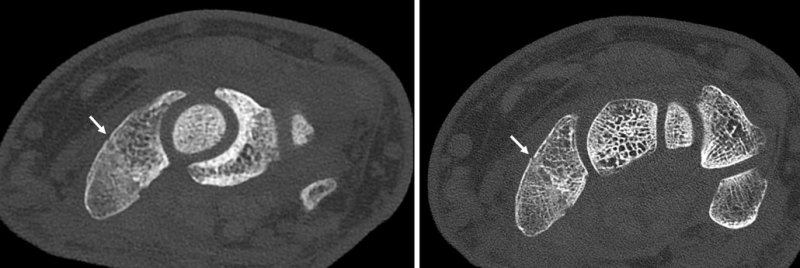

The X-ray detectors in CT scanners are the “secret sauce” of the technology, McCollough says, because the detectors are how the machines measure the X-rays in the first place. Most CT scanners measure that radiation indirectly, first converting the X-rays into visible light and then converting that light into an electric signal. A new era of CT technology is cutting out the middleman. In September, the U.S. Food and Drug Administration OK’d the first “photon-counting” CT scanner.

X-rays are a type of high-energy light, and like all light, they are made up of particles called photons. Photon-counting CT scanners measure individual X-ray photons. The technology also allows for crisper, more detailed images and provides a measure of the energies of the photons, which, like dual-energy CT, identifies different materials inside the body.